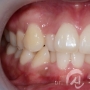

치아교정 치료사례